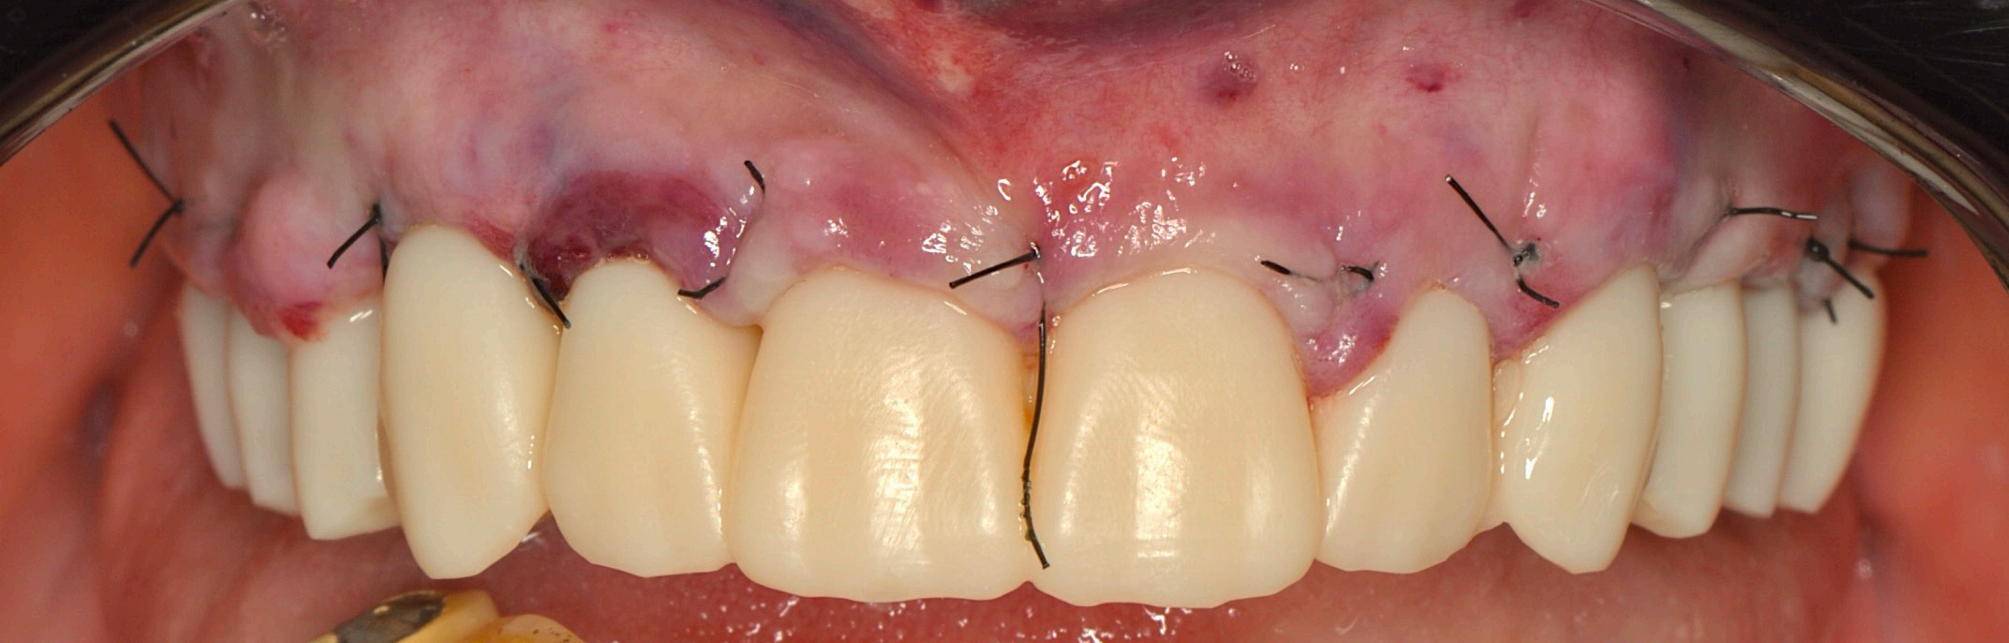

Preoperative and Planning •Fig. 1.1: Frontal intraoral view of the maxilla showing residual roots and fractured teeth. •Fig. 1.2: Occlusal intraoral view highlighting the compromised dentition. •Fig. 1.3: Digital wax-up integrated with a 3D facial scan and smile design guidelines. •Fig. 1.4, 1.5: Visualization of implant positions (16, 14, 12, 22, 24, 26) on a 3D model, prosthetically driven placement. •Fig. 1.6: 3D rendering of the wax-up aligned with the bone level, illustrating bone-prosthesis relationship.

The patient, a 70-year-old female, presented to the dental clinic with a chief complaint of compromised maxillary dentition and a desire for a fxed, aesthetically pleasing rehabilitation. Her medical history was unremarkable, with no systemic diseases, allergies, or medications reported, and her general health was deemed excellent for her age. Intraoral examination revealed a partially edentulous maxilla with failing dentition: residual roots were present at positions 13 (upper right canine) and 21 (upper left central incisor), while teeth 22 (upper left lateral incisor) and 13 exhibited fractures rendering them non-restorable (Fig. 1.1, 1.2). The patient expressed a strong preference for a fxed prosthesis that would restore both function and aesthetics, with a natural gingival contour as a priority.

Fig 4.1

Group 4: Immediate Provisionalization and Healing Fig. 4.1: Clinical photo of the 3D-printed provisional prosthesis inserted on the day of surgery. Fig. 4.2: Gingival healing at two months with emerging scalloped contours. Fig. 4.3: Application of BlueM gel for tissue and prosthesis disinfection. Fig. 4.4, 4.5: Post-cleaning views of healthy gingival tissues.